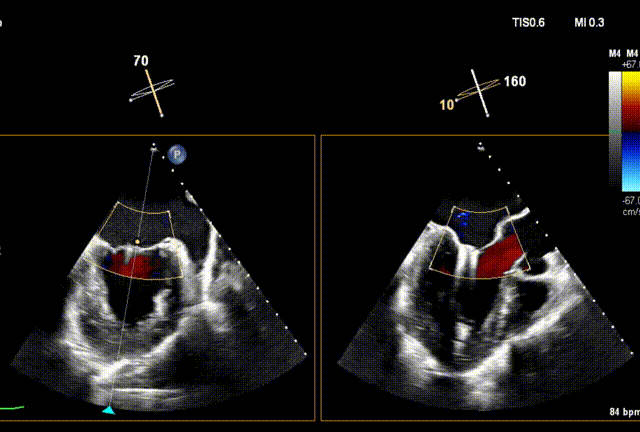

术前经食道超声(TEE)评估

术前TEE

DMR P2脱垂连枷(脱垂范围:12mm,连枷间距:3mm),反流2区,MR重度(VC:4* 10mm),A2:21mm,P2:10mm,AP:30mm,MVA约 4.7 cm²。